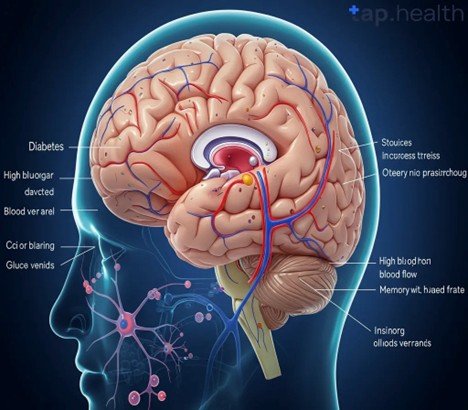

Understanding Diabetic Foot Ulcers

DFUs are open wounds or ulcers that usually develop on the lower part of the foot in diabetic patients. They ocurr due to diabetes complications like peripheral neuropathy (nerve damage), lack of circulation (ischemia), and infection. These ulcers are severe as they raise the susceptibility of infections. It may result in hospitalization, amputation and severe health complication without treatment.

· Poor glycemic control, infection severity, ischemia, and neuropathy aggravate prognosis.